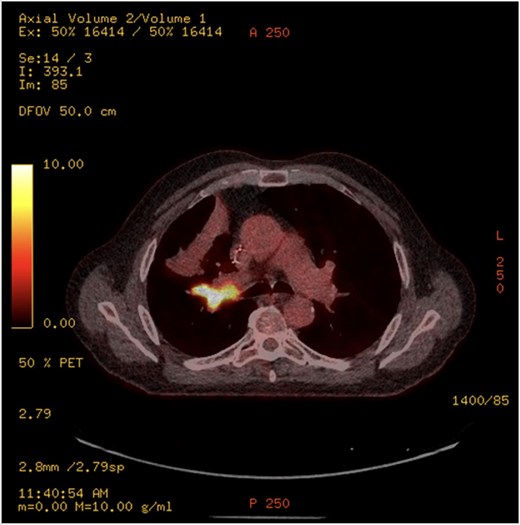

This 78-year-old man initially presented with a chest infection in October 2024, where a chest X-Ray (CXR) showed right upper lobe (RUL) consolidation accompanied by a pleural effusion (Fig. 1). He had no other symptoms, including haemoptysis, shortness of breath, fever, anorexia, or weight loss. A follow-up computed tomography (CT) chest 6 weeks later revealed a large endobronchial lesion in the right main bronchus, resulting in consolidation and partial collapse of the RUL (Figs 2 and 3). He went on to have a positron emission tomography (PET) scan (Fig. 4), CT head, bronchoscopy, and endobronchial ultrasound (EBUS). Imaging revealed a 3.8 cm lesion in the right upper lobe bronchus, which was mostly occluded. The biopsies showed evidence of a myoepithelial carcinoma, a rare pulmonary neoplasm.

PET-CT showing an endobronchial lesion that measures 3.8 × 2 cm and is fluorodeoxyglucose avid (SUV max 13.8 g/ml).

PET imaging may offer additional diagnostic insight. Rosen et al. [4] reported two cases with hypermetabolic activity [standardised update value (SUV) 6.6], consistent with our case which demonstrated an SUV of 13.8, suggesting high metabolic activity despite the tumour’s indolent histogenesis. However, the role of PET in staging and surveillance remains undefined due to limited data.

The imaging features of myoepithelial carcinoma of the lung are not well described in the literature. Routine imaging included chest X-ray, and CT scans were done in all the cases reviewed in the literature. On CXR, lesions typically appear as non-specific opacities or shadows. CT findings are more variable, ranging from smooth, well-circumscribed heterogeneous masses to solid spiculated or nodular lesions with irregular borders. This variability complicates preoperative differentiation from other bronchial neoplasms [4]. PET imaging may offer additional diagnostic insight. Rosen et al. [4] reported two cases with hypermetabolic activity (SUV 6.6), consistent with our case, which demonstrated an SUV of 13.8, suggesting high metabolic activity despite the tumour’s indolent histogenesis.